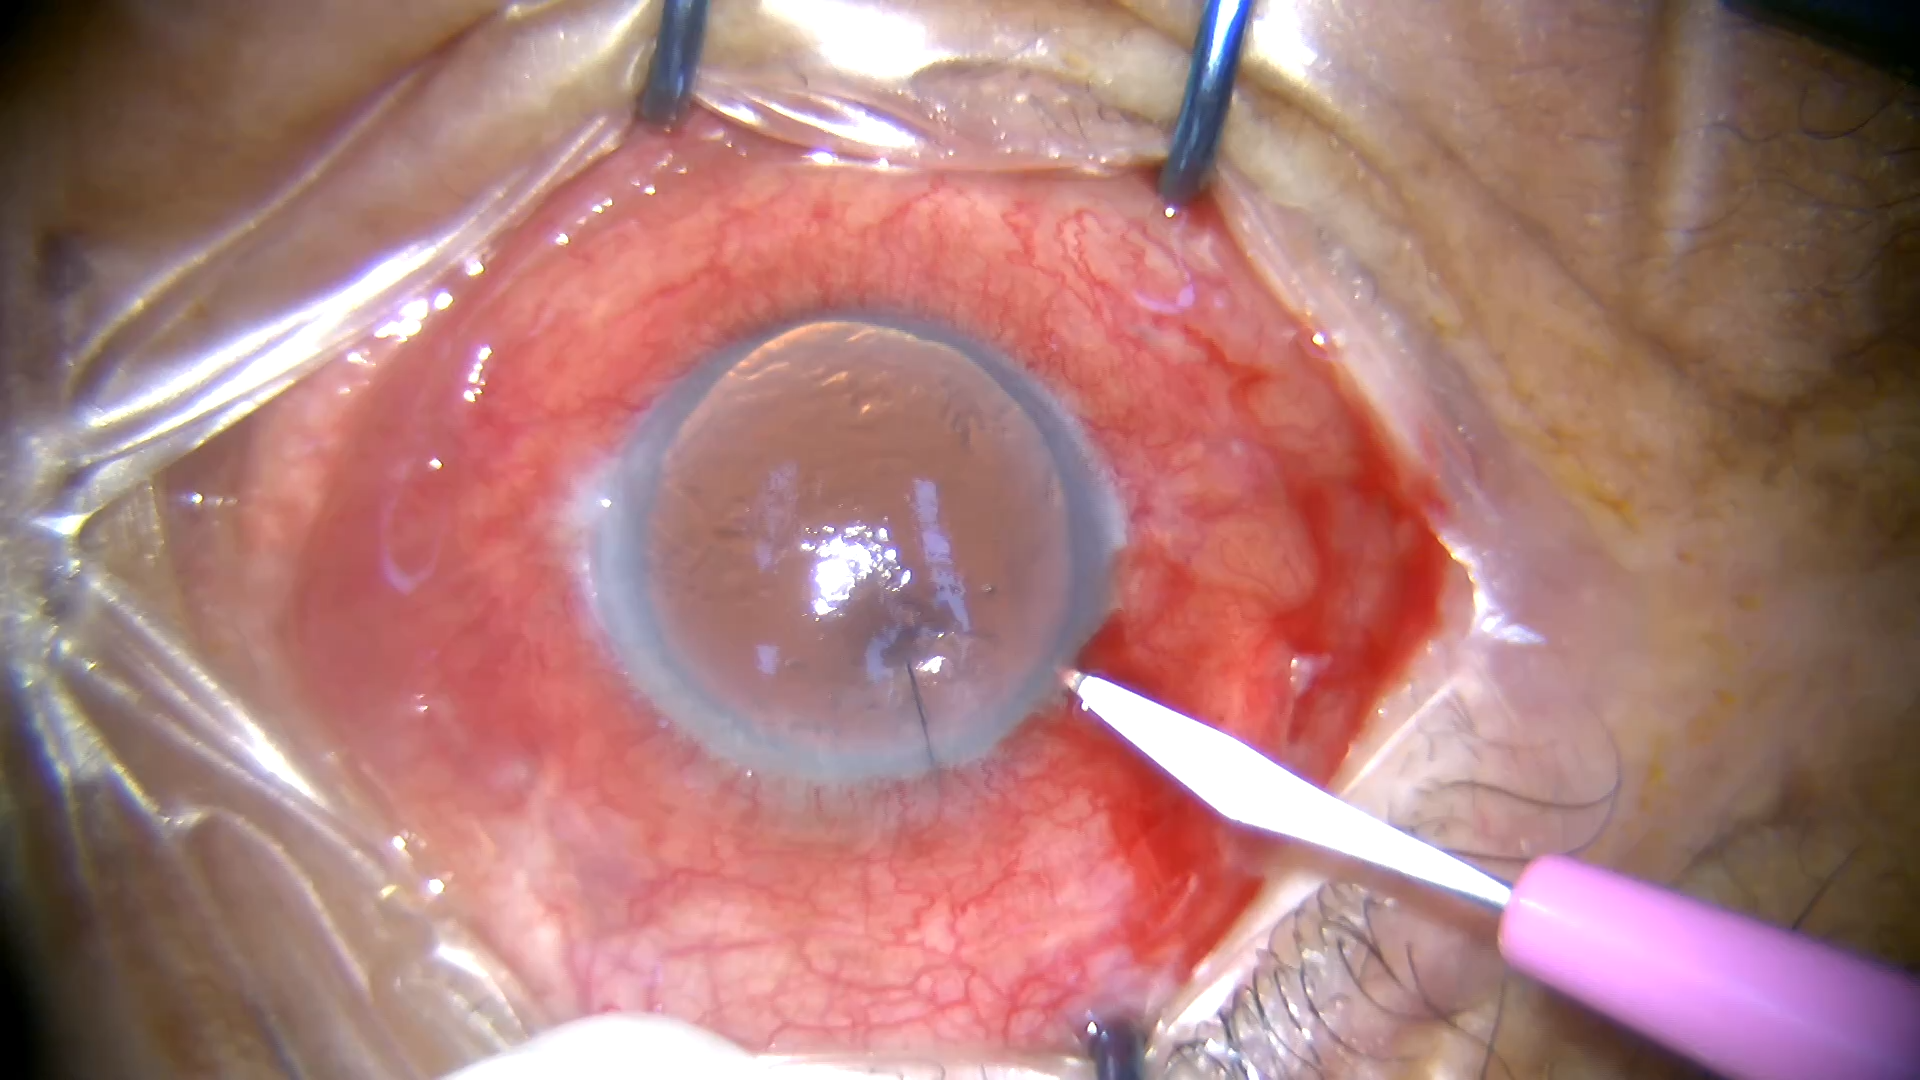

号外号外,湖南省人民医院副院长祖雄兵和眼科主任医师曾琦被指存在不正当关系,并有不雅视频传出。对此,医院工作人员回应:组织正在调查,请给医院宣传部门联系。当地卫生健康委员会对此回应:暂未接到相关的信访反映。祖雄兵为湖南省人民医院副院长,泌尿外科学科带头人。曾琦,博士,主任医师,硕士研究生导师。现任湖南省人民医院眼科副主任、眼科一病区主任,湖南省卫生健康高层次青年骨干人才,湖南省预防医学会眼病防治专业委员会主任委员、湖南省女医师协会眼科专业委员会主任委员、湖南省医学会眼科学专业委员会防盲学组副组长、湖南省医学会眼科学专业委员会眼外伤及职业病学组副组长、湖南省医学会眼科学专业委员会白内障学组副组长、